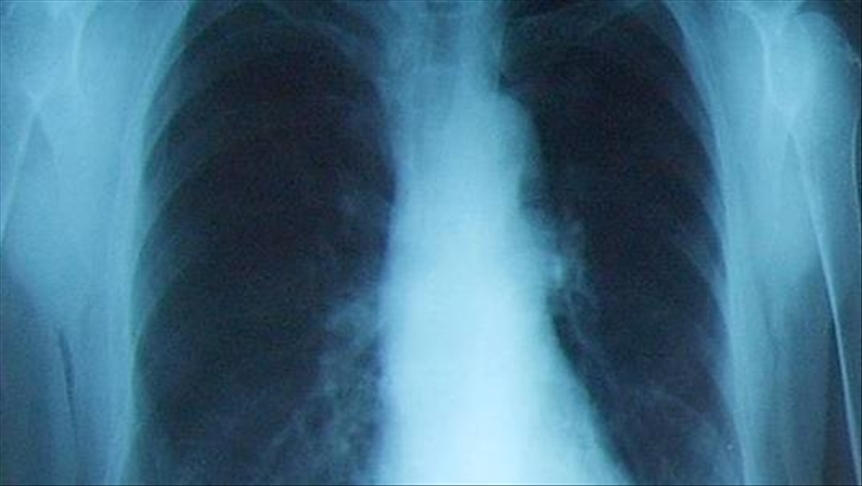

Doctors in India are urging stringent measures to tackle air pollution, believed to be one of the causes of a rise in lung cancers in the country.

In the last few years, India has been suffering from air pollution, with doctors fearing it will further deteriorate health problems, including lung cancer.